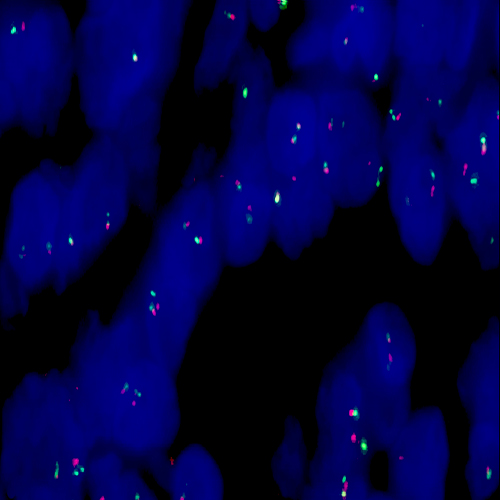

Diffuse Large B-Cell Lymphoma stained using Kreatech IGH (14q32) Break

XL probe for BOND (KBI-XL007).

IGH (14q32) Break - XL for BOND FISH probe detects genomic translocations involving the IGH gene. IGH (14q32) Proximal - XL and IGH (14q32) Distal - XL probes are optimized to detect the genomic regions proximal and distal to break points in the IGH gene region.

When combined, both probes are used to detect translocations involving the IGH gene at 14q32.